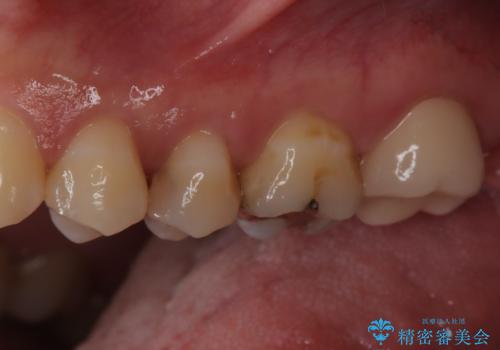

【セラミックインレー】虫歯の治療

- 定期検診にて虫歯を認めたため、セラミックインレーにて治療を行いました。

治療時にはラバーダムを装着しております。